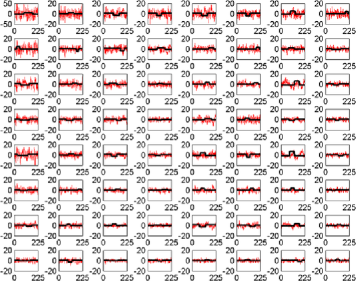

The subject in Figure 3 seems to exhibit strong deviations from stationarity—in fact, the -value associated with this subject is below based on the bootstrap test given in Section 7. It should be stressed that the change detection is a global hypothesis test combined over all components considered. In this way, while taking more components will help increase the chance that the change is present in one, it will come at the cost of the size of the change needed in finite samples for an omnibus test of this type. However, the subject shown in the figure did cause a rejection of the null hypothesis of no change both in the 64 and 125 subspace size omnibus tests. While the pictures in Figure 3 indicate that an epidemic change is indeed a good first approximation for the nonstationarities occurring for this particular subject, more deviation (maybe more change-points) does seem to be present. In Figure 4, a second subject is shown with a much smaller deviation from stationarity (most of the components seem to have little to no possible mean change present), which is significant but does not survive the false discovery rate (FDR) correction (see Section 4.3).

When testing subject 48501 from the connectome data, from whom the components can be seen in Figure 4, an epidemic change seems to be quite a good model for several components, but only a small part of the time series deviates from stationarity. For example, component 7 in Figure 6 shows a less pronounced but still plausible epidemic change compared with component 23 of subject 01018 in Figure 5. However, as can be seen in another component (Figure 7) from subject 48501, some of the components seem to be stationary without any change present.

Given that nearly 200 subjects were tested, a multiple comparison correction was implemented using the independent FDR method by Benjamini and Hochberg (1995). The use of an independent FDR is based on the fact that the comparisons are being taken across subjects who can be assumed to be independent of each other. Subject 01018 (Figure 3) survived the FDR correction and evidence was still found of nonstationarities being present. Subject 48501, whose projections are seen in Figure 4, also rejected the null hypothesis but only at about a 3% level, hence not surviving the FDR correction.